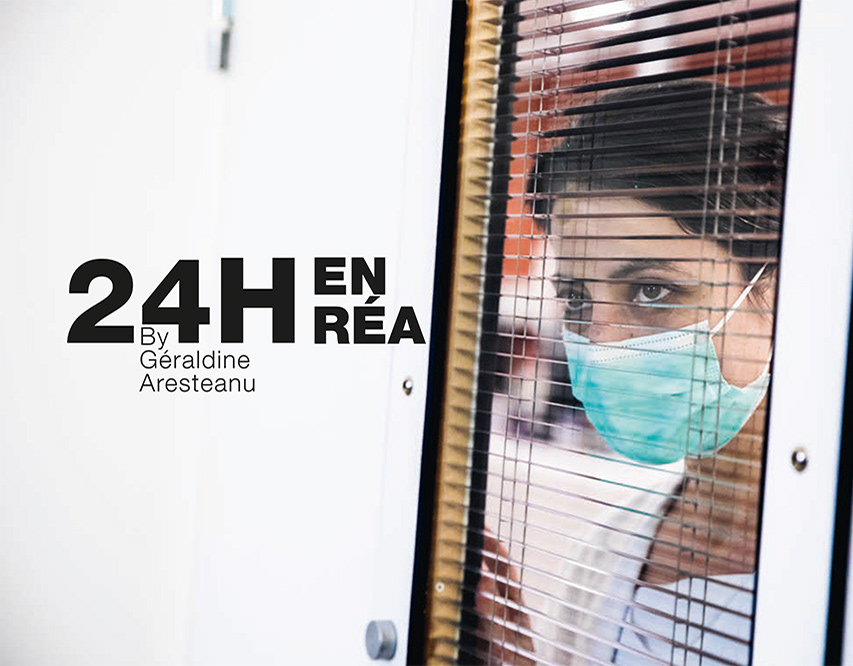

24H en réa, Géraldine Aresteanu